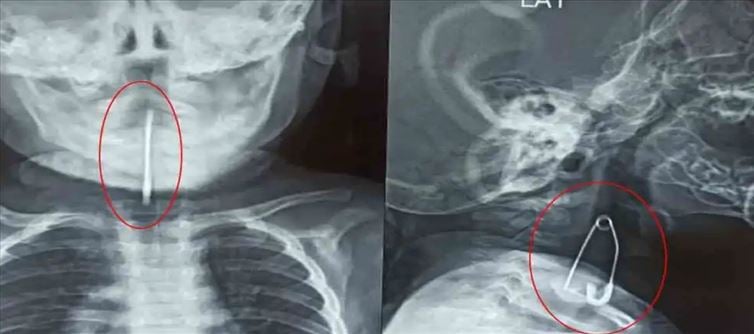

అయితే అటు బాలుడు మాత్రం ఎంతకీ ఏడుపు ఆపలేదు. కలకత్తా మెడికల్ కాలేజీకి తీసుకువెళ్లారు తల్లిదండ్రులు. ఈ క్రమంలోనే అక్కడ వైద్యులు ఆ బాలుడిని పరీక్షించారు  అయితే ఎక్స్రే తీయగా శ్వాసనాలంపై పిన్నీసు ఉన్నట్లు గుర్తించారు వైద్యులు. ఈ క్రమంలోనే బాలుడికి 45 నిమిషాల పాటు సర్జరీ చేసి ఆ పిన్నిసును విజయవంతంగా తొలగించారు. ప్రస్తుతం బాలుడు ఆరోగ్య పరిస్థితి  నిలకడగానే ఉంది అన్నది తెలుస్తుంది. ప్రస్తుతం ఊపిరి తీసుకోవడంలో బాలుడు ఎక్కడ ఇబ్బంది పడటం లేదని వైద్యులు స్పష్టం చేశారు.